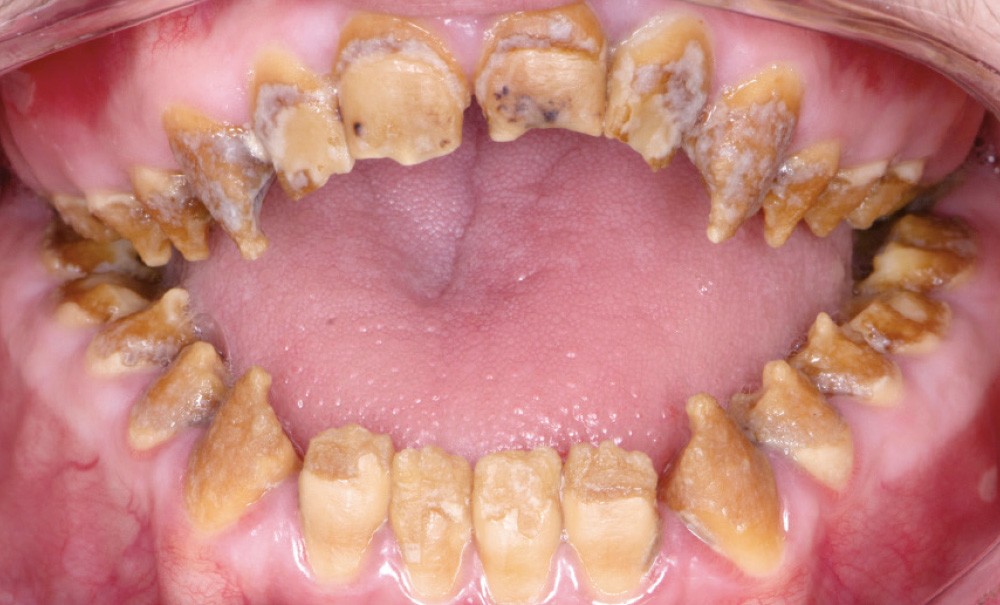

Dans tous les cas, le préjudice de l’enfant ou de l’adulte est non seulement fonctionnel – caractérisé par des sensibilités dentaires plus ou moins accrues, des malpositions occlusales associées parfois à une perte de dimension verticale – mais aussi esthétique, par l’aspect plus ou moins coloré et malformé des dents (fig. 1a, b). Le retentissement psychologique est variable selon la sévérité de l’atteinte et l’environnement social, mais reste important, surtout dans l’enfance [3].